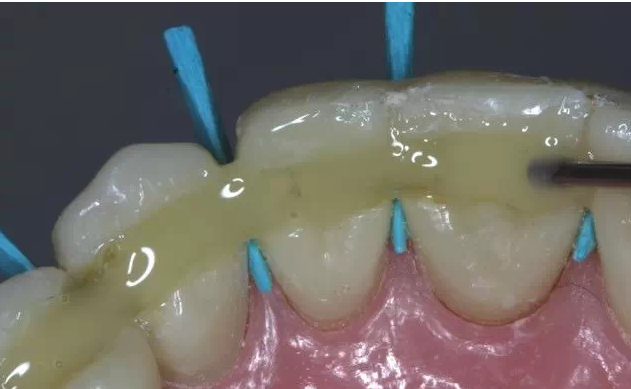

這是牙周病常規(guī)的治療方法,清除或控制臨床炎癥和致病因素,去除病因,消除炎癥。包括口腔衛(wèi)生宣教、充填齲洞、口腔潔治刮治、牙體牙髓治療、咬合調(diào)整、去除不良修復(fù)體、藥物治療(輔助手段,局部用藥效果好)、拔除治療效果不佳的牙周病患牙等。

牙周炎發(fā)展到一定階段時(shí),僅采用基礎(chǔ)治療難以取得較好療效,必須通過(guò)適時(shí)而合宜的手術(shù)治療挽救患牙,才能保持牙周組織健康,延長(zhǎng)患牙在口腔內(nèi)的壽命,維持牙列的完整性,促進(jìn)全身健康。其手段包括齦下刮治、根面平整、牙周翻瓣術(shù)、牙齦切除術(shù)、牙周夾板固定術(shù)等。